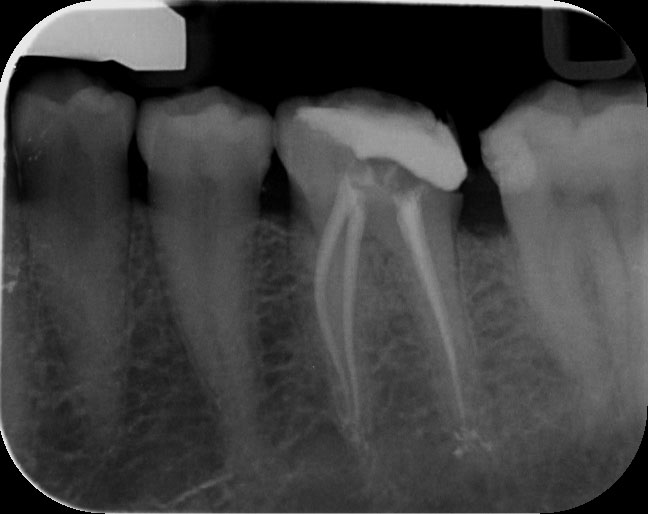

Un diente endodonciado es siempre más débil que un diente vital, pero es siempre mejor que un diente doloroso o infectado.

Debemos saber que la endodoncia de una pieza es necesaria cuando:

En ocasiones, el tratamiento de endodoncia no es suficiente para eliminar la infección existente en el hueso alveolar y se hace preciso realizar una Apicectomía mediante una pequeña cirugía en el extremo de la raíz. Para ello es necesario que previamente esté realizado el tratamiento endodóntico.